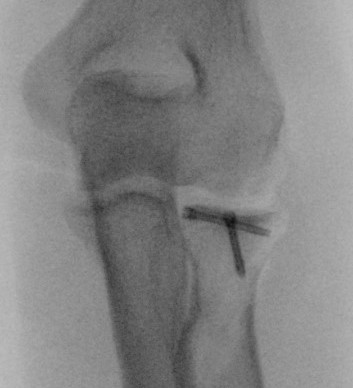

- check no overstuffing on xray

Overstuffing

| Lesser sigmoid notch | Symmetry of ulnohumeral joint |

|---|---|

|

Radial head shoulder articulate with lesser notch

Ensure no gapping of lateral ulnohumeral joint |

- cadaveric study

- increased medial ulno-humeral joint line gapping with overlengthening of 6 or 8 mm

- increased lateral ulno-humeral joint line gapping with overlengthening of 2 mm